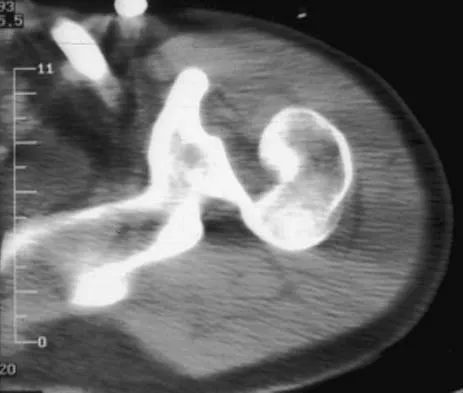

A 30-year-old woman injured her ankle playing soccer 3 months ago. She now reports popping and pain over the lateral side of her ankle. An MRI scan is shown in Figure 33. What structure needs to be repaired to alleviate the popping?

Explanation

The symptoms and MRI scan indicate dislocated peroneal tendons. In this patient, the structure that needs to be repaired is the superior peroneal retinaculum. If the popping was coming from a torn peroneal tendon, repair would involve the peroneal longus or brevis tendon, but this is not shown in the MRI scan. The anterior talofibular ligament or the calcaneofibular ligament would need to be repaired if the patient had ankle instability due to an ankle sprain. Jones DC: Tendon disorders of the foot and ankle. J Am Acad Orthop Surg 1993;1:87-94.